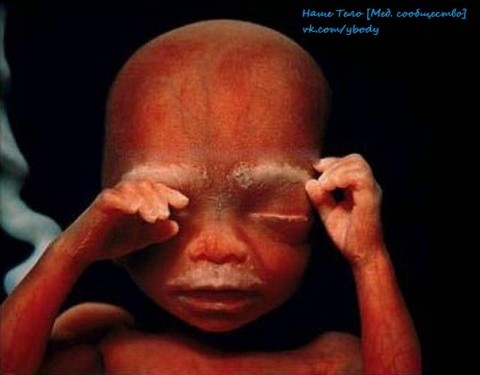

6 месяцев. Впереди еще восемь-десять беззаботных недель

36 недель. Через 4 недели ребенок увидит белый свет Источник